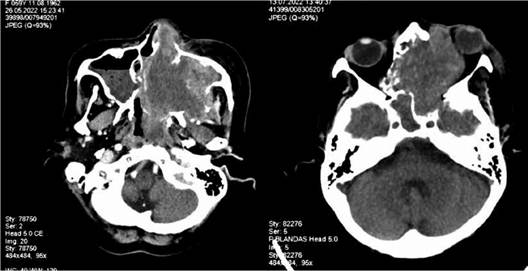

La tomografía con contraste reportó seno maxilar izquierdo con lesión de densidad de partes blandas, medidas 103 x 96 x 69 mm, con realce heterogéneo ocupando la totalidad del seno con extensión a celdillas etmoidales que comprometía la luz de fosa nasal izquierda y disminución de luz nasofaringe del 50 %; además, se extiendía a cavidad orbitaria izquierda provocando desplazamiento de músculos mediales; con destrucción ósea, sin evidencia de adenopatías en otro sitio (Figura 5) sin infiltración a médula ósea. Ecocardiograma reportó insuficiencia mitral/tricúspidea leve con FEVI 57%.

Tomografía con contraste no revela lesiones estructurales a nivel craneal. Se evidenció adenopatías en región cervical bilateral y submentoniana (el mayor de 3 cm); en mediastino región paratraqueal y paraaortica derecha, región axilar bilateral (3x5 cm), retroperitoneal e inguinal bilateral (el mayor de 3x7 cm) (Figura 6). Se realizó quimioterapia de acuerdo a protocolo SMILE, con respuesta desfavorable.